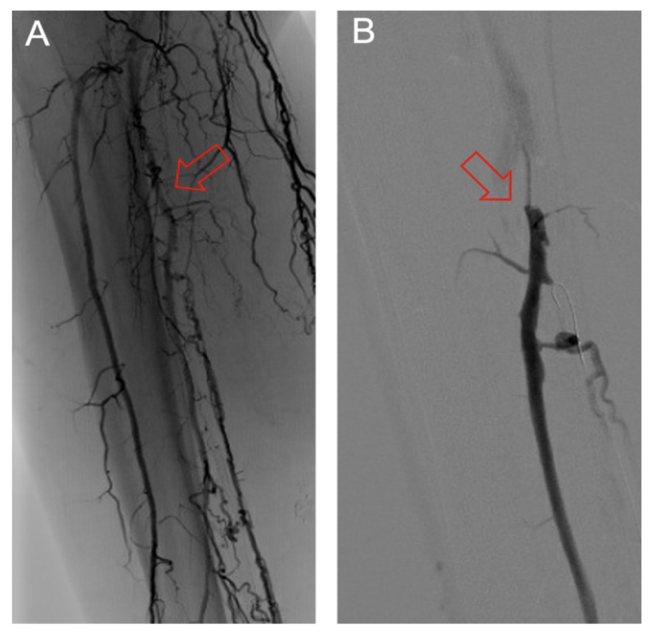

The frequency of DVA failure types in our cohort is presented in Table 2. Examples of angiography imaging for each failure type are presented in Figures 2-6. The frequencies of Type 1a and Type 1b failures (Figure 2) were 44.0% and 16.0%, respectively. A Type 2 intragraft failure was demonstrated in 32.0% of the cohort (Figure 3). Among the venous outflow lesions, 24.0% were Type 3a, 24.0% were Type 3b, and 8.0% were Type 3s (Figure 4). Fifty-two percent of cases demonstrated a Type 4 failure of the venous arch (Figure 5). Four percent of reinterventions were Type 5 undefined. Two-thirds of the reintervention group presented with multiple failure types concurrently (Figure 6). Sixty-eight percent of repeat cases were due to lesions in the venous outflow (Types 3 and 4), and 56.0% of cases demonstrated arterial inflow lesions (Type 1).

Recognizing causes of DVA failures in our study had implications for management. Type 1 failure patterns were approached with plain old balloon or DCB angioplasty. Retrograde access into the DVA stent-graft conduit facilitated these procedures and allowed recreation of the proximal arterial-venous connection if an occlusion at this location could not be traversed with a wire. Type 2 failures (Figure 3) were treated with PTA and/or placement of an additional stent-graft to cover resistant lesions. Type 3 lesions (Figure 4) were managed with PTA, caudal extension of the original stent-graft, or use of a Supera woven nitinol bare-metal stent in the transitional vein. Notably, crossing the distal stent edge and transitional vein lesions with an antegrade approach was not possible in some cases, necessitating repeat retrograde venous pedal puncture for bidirectional crossing and wire rendezvous to complete the reintervention successfully. As a result of this experience, we routinely prep the foot for all reinterventions and quickly adopt a retrograde approach if initial wire crossing is a challenge. Type 4 (Figure 5) are addressed with PTA or DCB, although venous arch reocclusion can be difficult to traverse with catheter-wire techniques, and in 1 case resulted in a failure to restore DVA flow. For cases with combinations of failure types, multiple treatment modes may be indicated based upon each lesion type (Figure 6).